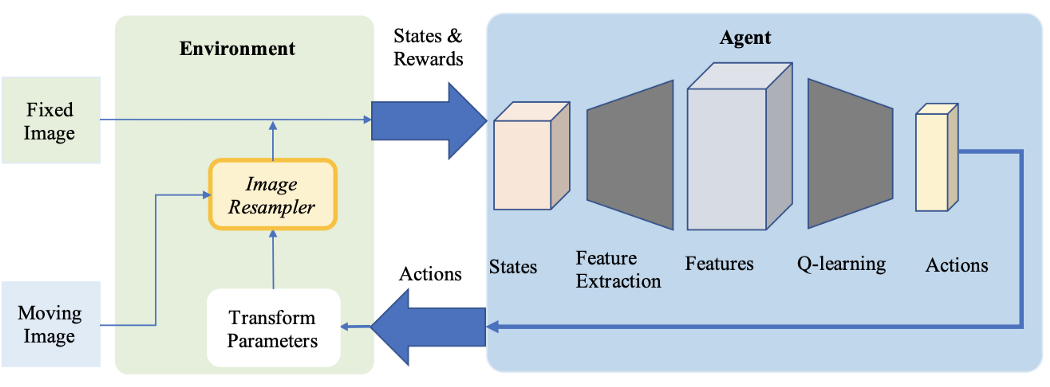

强化学习

强化学习方法作为医学应用的常用方法正在得到越来越多的关注。与预定义的优化算法相反,在这种方法中,我们使用训练好的代理进行配准。

强化学习方法的配准可视化

- 2016年,Liao 等人首先使用强化学习进行图像配准。他们的方法基于有监督算法进行端到端的训练。它的目标是通过寻找最佳的运动动作序列来对齐图像。这种方法优于最先进的方法,但它只能用于刚性转换。

- 强化学习也可以用于更复杂的转换。在Robust non-rigid registration through agent-based action learning论文中,Krebs等人使用人工代理优化变形模型参数。该方法对前列腺MRI图像的患者间的配准进行实验,在2-D和3-D中表现出了较好的结果。